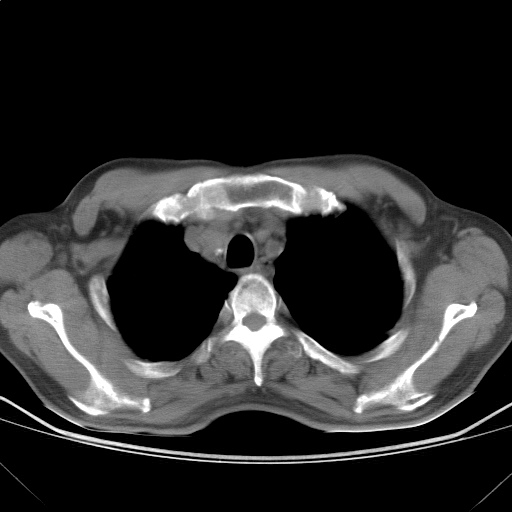

以下是引用随光逐影在2009-5-1 13:53:00的发言:[br]考虑为:1)两肺血行播散型肺结核;2)右肺下叶炎症感染。3)右侧胸膜增厚。